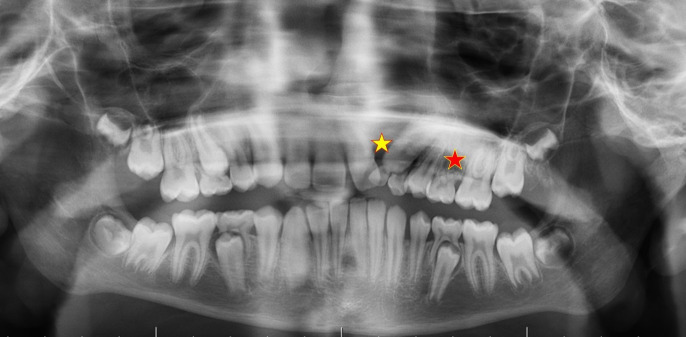

Objectives: Dental agenesis refers to the absence of one or more teeth, occurring in both primary and permanent dentitions. It can result in several complications, impacting functional aspects of the dentition, such as chewing and speech. This study aimed to evaluate the prevalence of agenesis of permanent incisors, premolars, and third molars in patients aged 8-18. The prevalences were compared according to age, gender, and the regions they live in.

Material and methods: This study was conducted in the Central Anatolia and Mediterranean regions of Turkey. It included data from 593 patients, 304 females and 289 males. The study involved a retrospective evaluation of the patients' orthopantomographic images. Descriptive statistics were employed for the analysis.

Results: In the study, the prevalence of incisor agenesis among all patients was 2.4%. Premolar agenesis was found in 3.9% of patients, with the mandibular second premolar being the most commonly missing premolar (missing in 19 patients). The prevalence of third molar agenesis was 19.9% (118 patients). Incisor and premolar agenesis were more common in the Central Anatolia region than the Mediterranean region, whereas third molar agenesis was more prevalent in the Mediterranean region. In both regions, the left mandibular premolar was the most frequently missing premolar tooth, and the left maxillary third molar was the most frequently missing third molar tooth.

Conclusion: This study presents a thorough analysis of the prevalence and distribution of tooth agenesis, with a particular focus on incisors, premolars, and third molars. The results emphasize the necessity of considering gender differences and specific tooth locations in the diagnostic and therapeutic approaches to tooth agenesis.